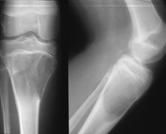

Kemiğin selim-agresif tümörü olarak kabul edilir. Genç erişkinde osteolitik karakterde kemik tümörüdür. Uzun kemiklerin ekleme yakın uç kısmından çıkabilir. Hastalar tümör bölgesinde devamlı ve giderek artan inatçı bir ağrı ve şişlik ile başvururlar.Sadece küretaj yapılan hastalarda yüksek lokal nüks yanında akciğer metastazı yapma potansiyeli olduğundan lokal agresif tümör olarak kabul edilir. Ama bu metastazlar ölümcül değildir.Diz eklemi en sık tutulan bölgedir. Diğer sık tutulan bölge el bileğidir. Kemik korteksini harap ederek yumuşak dokulara yayılım gösterebilir. Tanı için biyopsi şarttır. Brown tümörü ile ayırıcı tanısı yapılmalıdır. Tanı esnasında akciğer tomografisi çekilmelidir.